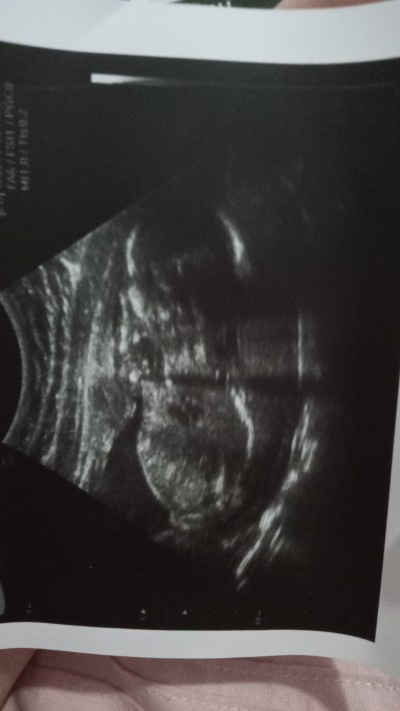

ben yüze benzettim

Gebelik haftası 20+3

Arkasi donuk diye gordum eger yanlis anlamadiysam cunku bende pek.anlamam :)

Bn onu olarak gordum erkekmi

Kiz dediler %100

Yan yatmış bence

Yan yatıyr canm

Erkeğe benzettim yüzü falan gozukuyo

Yan yatmış kuzum

Soruları beğenmeyip  sacma bulanlar cıkıp    daha mantıklı sorulara cevap verebilir ama  israrla neden bu soruyu  sordun derdine dusunuyor anlamiyorum canim bence  sirt dönmüs yatior yani yandan görünüyor gibi geldi bana:)

Popişi annesi arkasını dönmüş sanırsam yaa keyfe bak yaa <3:D

Sirt usdu yatmis beden kafa bile gozukur canm :))